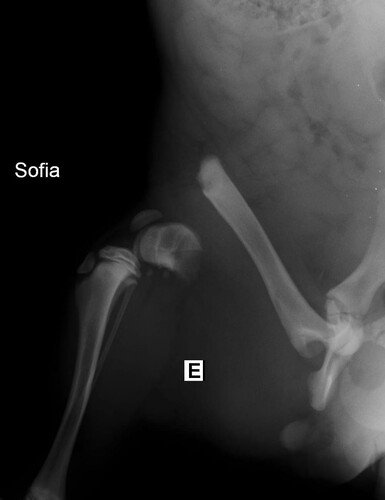

A primeira tia veterinária que me avaliou no dia 01/07, verificou através de exames de raio-x que eu estava com uma fratura muito feia na minha patinha traseira e disse que eu estava com muita dor. Ela falou que eu teria que ficar internada para tomar medicação e possivelmente realizar uma cirurgia na patinha. Além disso, com o resultado do exame de sangue, foi constatado que eu estava com anemia e alterações hepáticas.

No dia 03/07 tive uma consulta com o veterinário ortopedista e ele disse que aquele dodói não era uma fratura de atropelamento, e sim de ESPANCAMENTO. Ele também falou que eu precisaria fazer uma cirurgia para colocar implantes no ossinho da minha patinha e para a amputação da cabeça do fêmur. A tia que me resgatou perguntou ao ortopedista se eu ficaria com algum problema de mobilidade e ele disse que não devo ficar, mas que o ideal é eu fazer fisioterapia pós operatória.